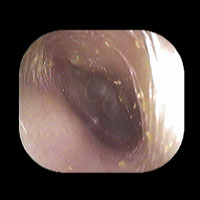

右急性中耳炎(中等症)

鼓膜がやや赤くなっています。鼓膜の奥に膿が透けて見えています。鼓膜の腫れはありません。抗生剤の内服で鼓膜切開を行わずに16日目で治りました。

7日目